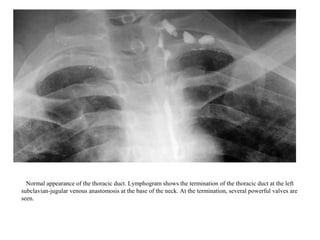

Normal appearance of the thoracic duct. Lymphogram shows the termination of the thoracic duct at the left

subclavian-jugular venous anastomosis at the base of the neck. At the termination, several powerful valves are

seen.

Normal appearance ofthe thoracic duct. Lymphogram shows the termination of the thoracic duct at the left subclavian-jugular venous anastomosis at the base of the neck. At the termination, several powerful valves are seen.